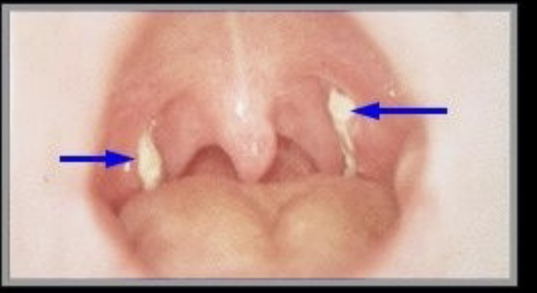

corynebacterium diphtheriae

from upper respiratory tract, humans only host. transmitted through inhalation. cytotoxic exotoxin blocks protein synthesis, enters blood & damages heart & CNS. if toxin not present, strain is not pathogenic. initial symptoms are sore throat, fever, & malaise. pseudomembrane forms in throat. myocarditis, suffocation